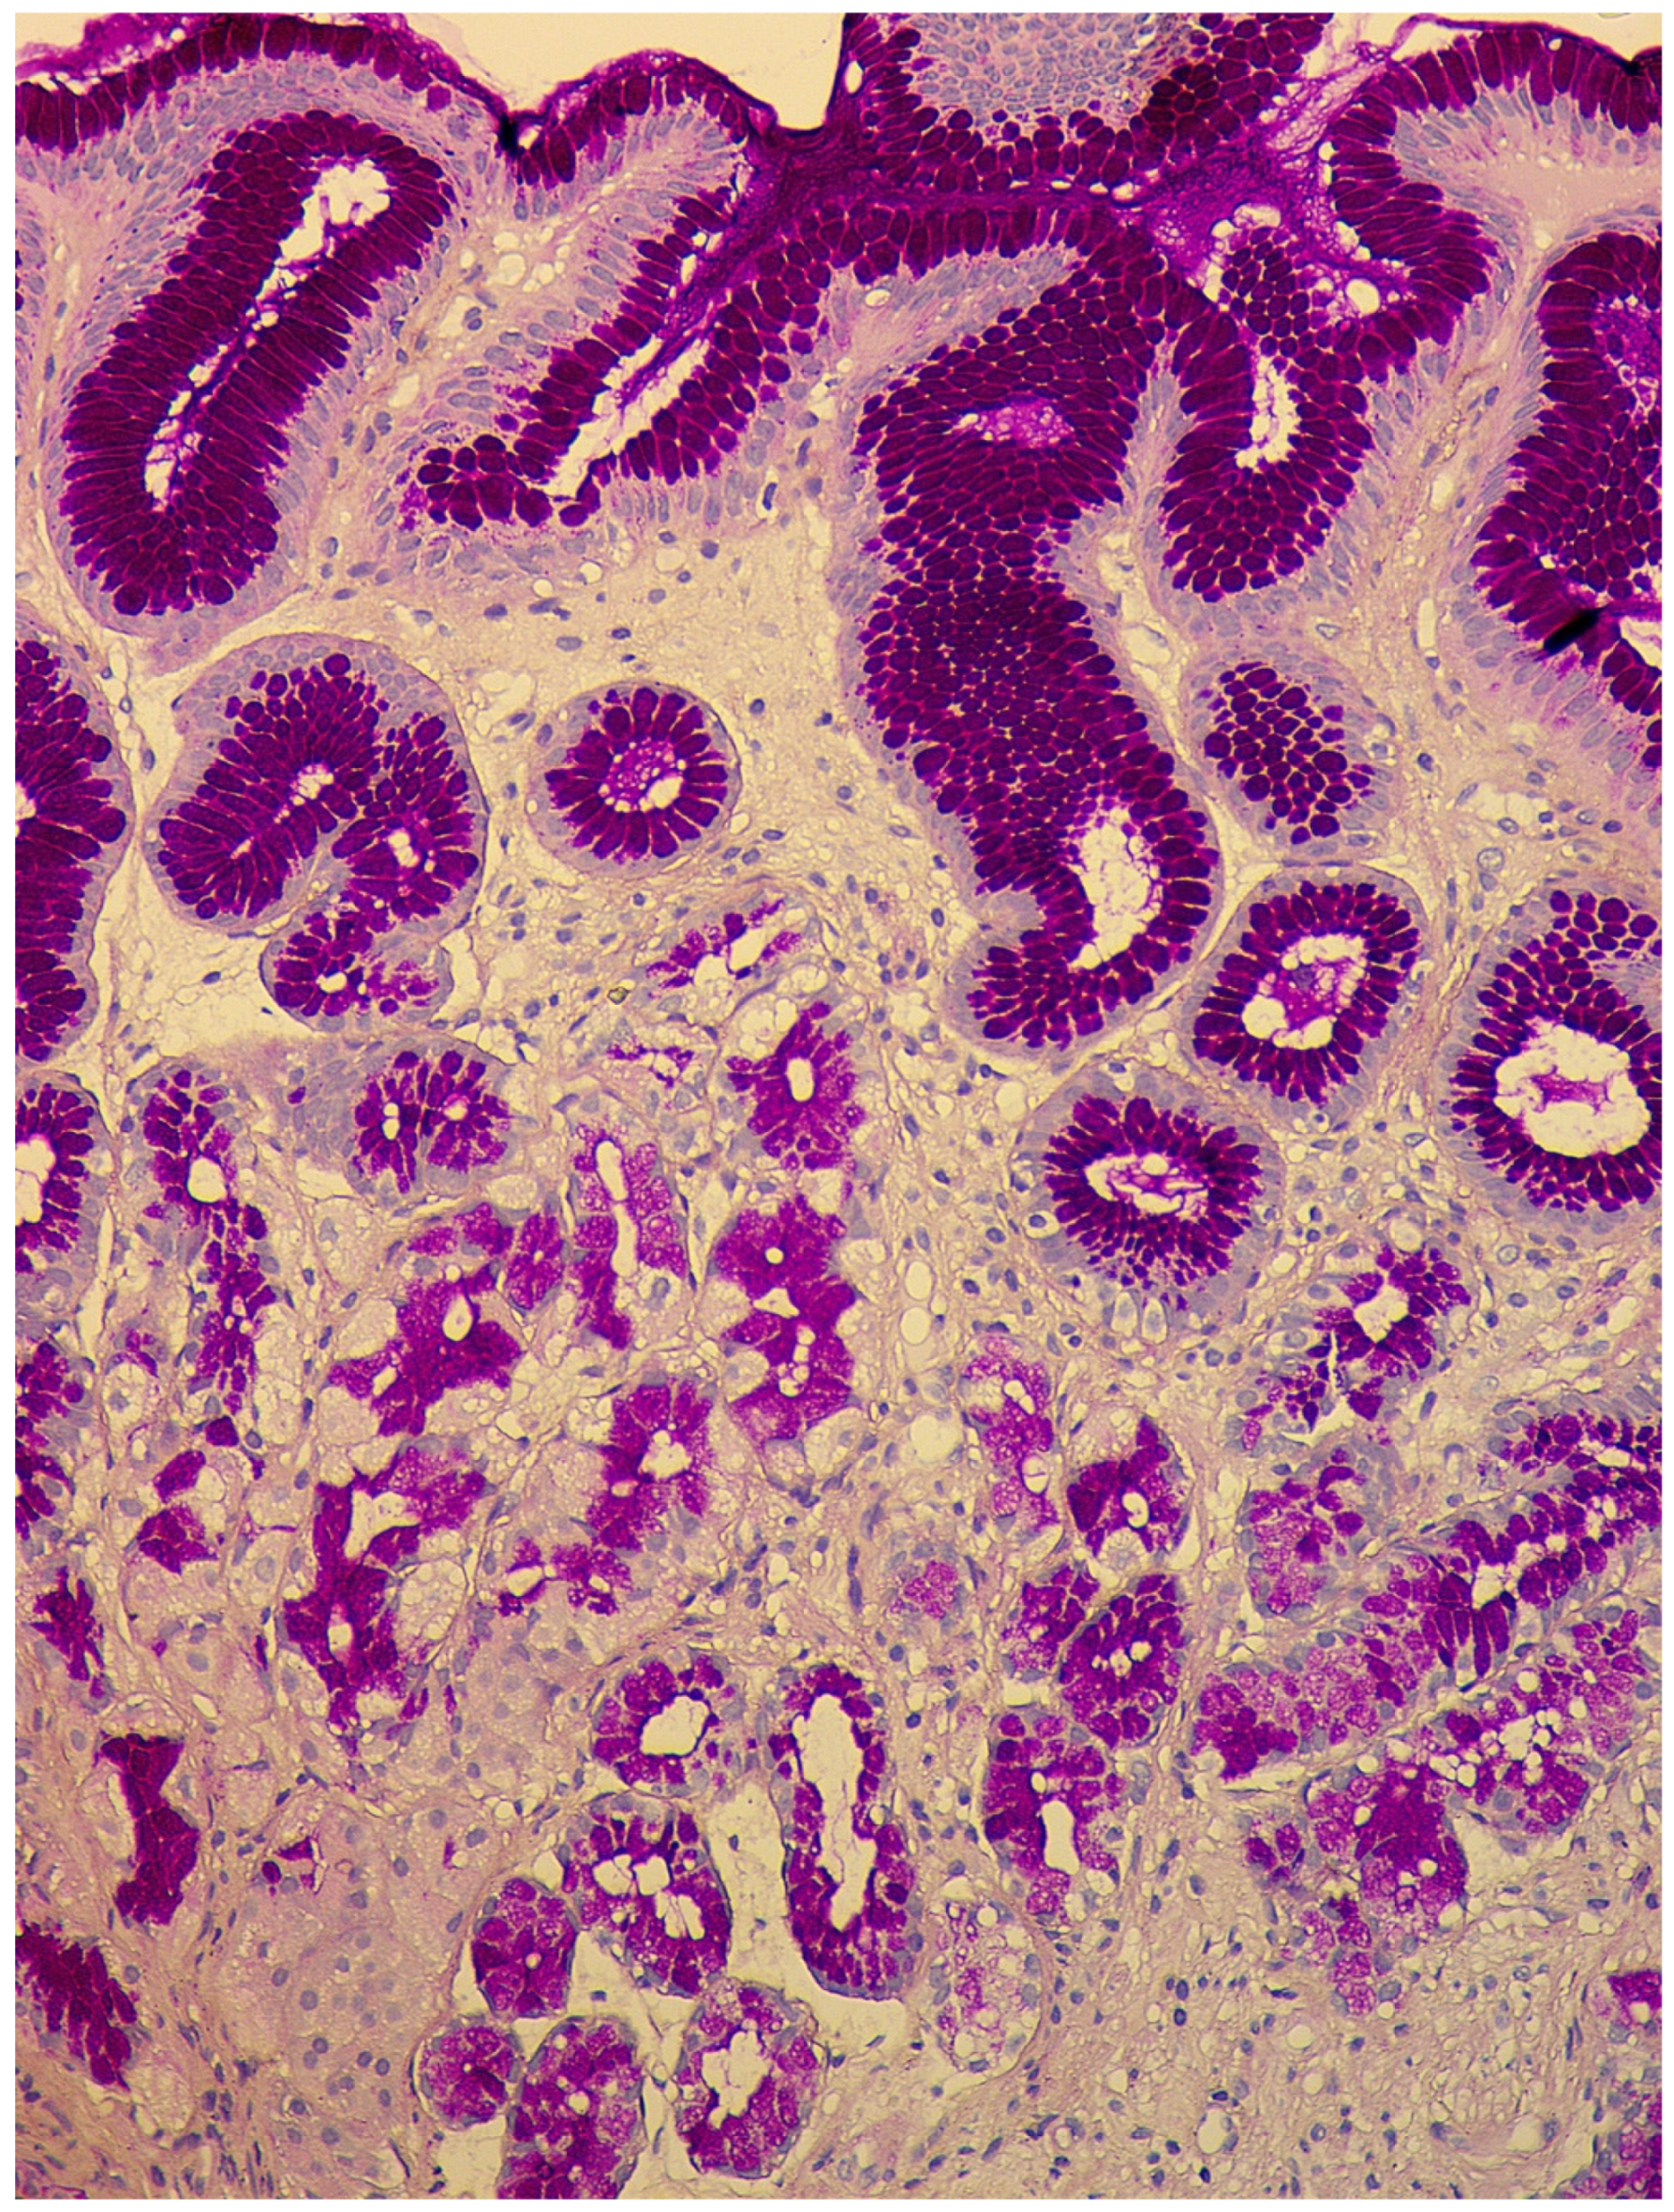

- Micronodular hyperplasia. The presence of the cells’ cluster in contact with the basement membrane, but not exceeding the diameter of the gland, up to 150 μm in diameter, or a similar cluster located freely in the lamina propria of the mucous membrane.

- Adenomatous (adenomatoid) hyperplasia. The presence of an aggregate of five or more clusters (Figure 5).

- Neuroendocrine cells dysplasia. Merging clusters with diameters of more than 150 µm but less than 500 µm.